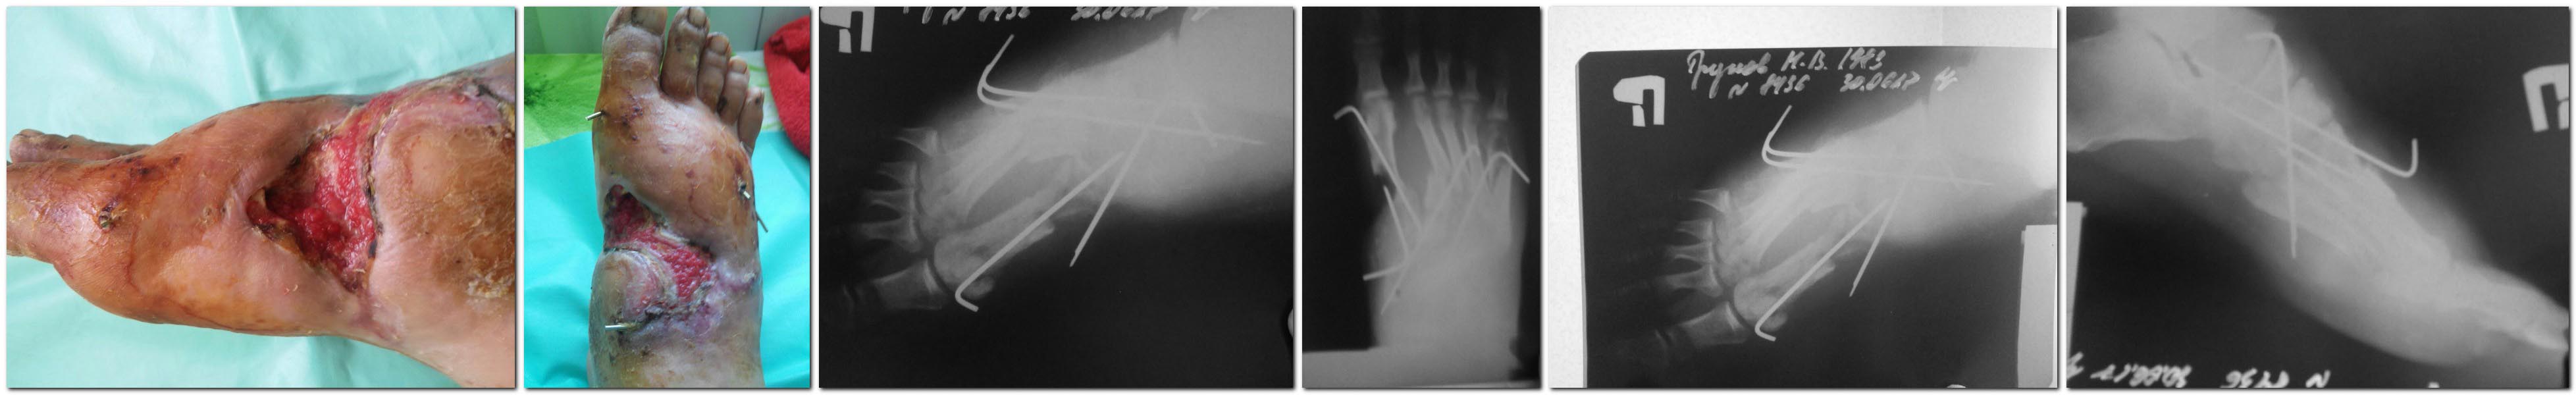

Здравствуйте уважаемые коллеги!Прошу поделиться соображениями по поводу

тактики лечения данного клинического случая.

Травма 27.04.17.- открытый перелом 1-5 плюсневых костей на уровне

оснований со смещением, дефект мягких тканей (со слов принимавшего доктора).

При поступлении выполнена ПХО с фиксацией спицами, далее перевязки и

несколько ВХО,на которых в т.ч. выполнена краевая резекция отломков 1

плюсневой кости.Сформировалась вялогранулирующая рана с м/тканным

дефектом и "обнажённой" 1 плюсневой костью. Да, пациент страдает

сахарным диабетом 2 типа.

Какие возможны варианты ведения на ваш взгляд? Что делать с 1 плюсневой

костью? Спасибо всем!